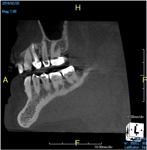

(8.) An original finding of a small lesion on the mesial root of tooth No. 30 was not accompanied by any outward symptoms; therefore, the patient delayed pursuing treatment. When a follow-up CBCT scan was acquired 6 years later, the easy-to-visualize increase in the dimensions of the lesion motivated the patient to elect a treatment plan.

Figure 8

(9.) An original finding of a small lesion on the mesial root of tooth No. 30 was not accompanied by any outward symptoms; therefore, the patient delayed pursuing treatment. When a follow-up CBCT scan was acquired 6 years later, the easy-to-visualize increase in the dimensions of the lesion motivated the patient to elect a treatment plan.

Figure 9